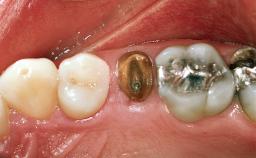

In the summer of 2002, a 42-year-old female patient was referred to the University of Geneva for the replacement of posterior maxillary and mandibular missing or non-restorable teeth.The patient’s medical history revealed no significant findings,and she was in good general health.Her dental history included recurrent decay that led to the loss of several posterior teeth. The patient showed no history of periodontal disease. At the extraoral examination, the patient presented normal physiognomy with normal facial and lip support and homogenous distribution of the facial thirds. At full smiling, the patient displayed an average lip line, and a tooth gap was slightly visible in the left maxilla. Small diastemas were present between the anterior maxillary teeth.